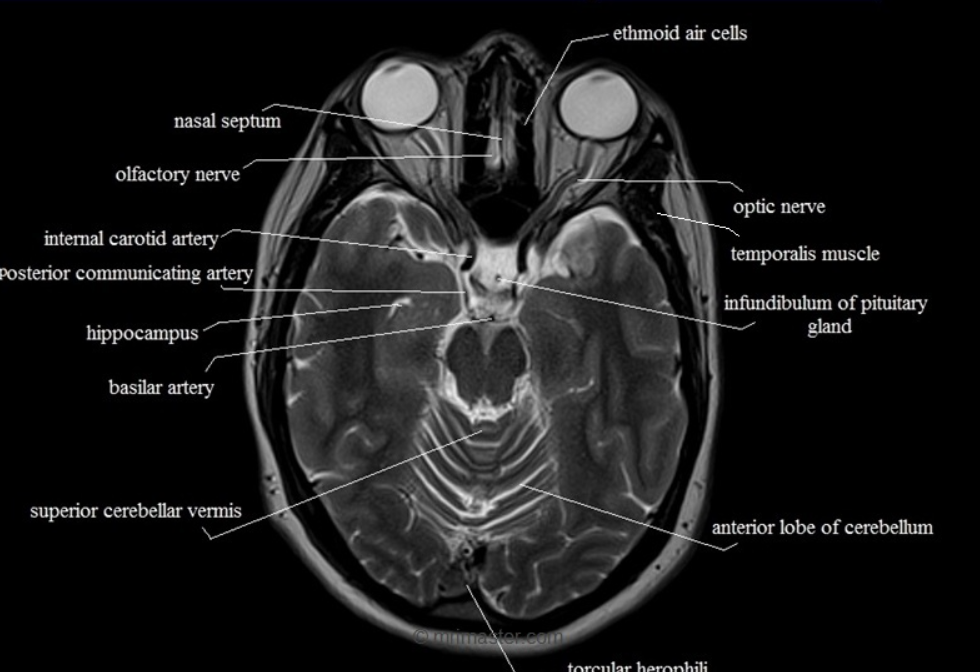

medulla는 소뇌가 나오기 전, pons는 소뇌 중간, midbrain은 소뇌의 윗부분 정도에 있다. 즉, 소뇌의 범위 안에 midbrain이 있는 것이다.

위 사진에 표기는 되어 있지 않지만 소뇌의 위쪽 끝부분 level에서 위의 중간 갈라진 부분이 midbrain이 아닐까 한다.